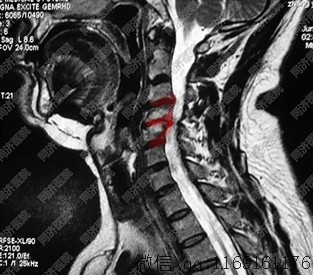

1.颈段脊柱由7个颈椎、6个椎间盘(1、第2颈椎间无椎间盘)和所属韧带构成。上连颅骨,下接第1胸椎,周围为颈部肌肉、血管、神经和皮肤等组织包绕,俗称“脖子”或“脖颈”。从侧方观察,颈椎排列呈前凸弧度。虽然颈椎在脊椎椎骨中体积最小,但它的活动度和活动频率最大,而且解剖结构、生理功能复杂,所以容易引起劳损和外伤,导致颈椎病。

2.除第1、第2颈椎结构有所特殊外,其余颈椎与胸、腰段椎骨大致相似,均由椎体、椎弓、突起(包括横突、上下关节突和棘突)等基本结构组成。椎体在前,椎弓在后,两者环绕共同形成椎孔。各椎孔目连构成椎管,其中容纳脊髓。椎体上面周缘的两侧偏向后方,有脊状突起,称为钩突。钩突与相邻的上一椎体下缘侧方的斜坡对合,构成钩椎关节(亦称椎体半关节——Iuschka关节)

此关节能防止椎间盘向侧后方突出,但当因退变而发生骨质增生时,增生的骨刺则可能影响位于其侧方的椎动脉血液循环,并可压迫位于其后方的神经根。钩椎关节退变可较早出现。由于该关节位于椎间边缘部,在颈椎作旋转等运动时,局部的活动度较大,两侧的钩状突起呈倾斜面,局部椎间隙较窄,颈椎活动所产生的压力和剪力常集中于此。椎弓根上、下缘的上、下切迹相对形成椎间孔,有颈脊神经根和伴行血管通过。通常颈脊神经仅占推间孔的一半,在骨质增生或韧带肥厚时,孔隙变小、变形,神经根就会受到刺激和压迫.产生上肢疼痛、手指麻木等症状。颈椎的横突较短,其中间部有横突孔,除第7颈椎横突孔较小外,其余均有椎动脉通过。当颈椎发生骨质增生等病变时,可导致椎动脉血液动力学方面的改变,影响大脑血液供应,产生眩晕、恶心等换状。